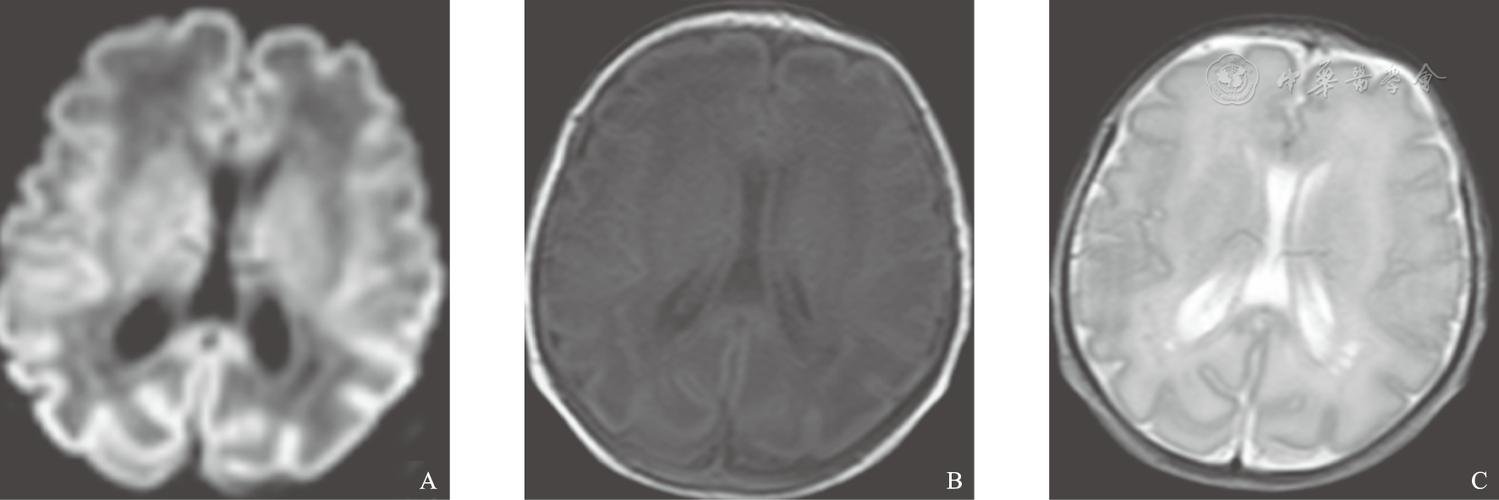

脑白质软化,脑白质脱髓鞘

脑室周围白质软化早产儿出生早期mri表现及其演变

认识早产儿疾病系列科普脑室旁白质软化

儿童脑白质软化症的影像学诊断.pdf 2页

脑白质病变影像诊断